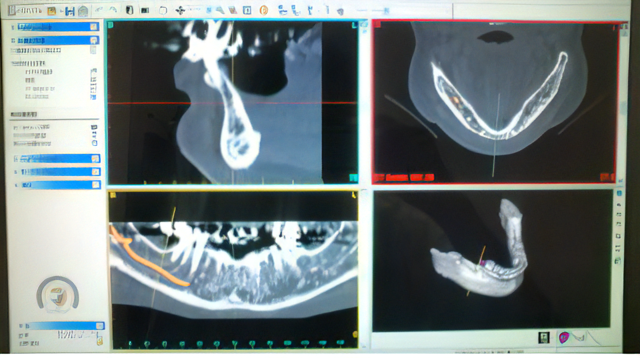

竹内歯科医院では、麻酔科医による全身の診査・診断を経てインプラントの適応の可否を判断しています。さらに、術前の3D歯科用CT検査は、あごの骨の状態や神経の位置などの正確な診断に欠かせません。近院のCTセンターや総合病院にて行っていただいたデジタルデータをもとに、竹内歯科医院にて綿密な治療計画やシミュレーションを行います。すべての計画書や見積り、CT解析結果は患者様が持ち帰ってご自宅で確認していただくことも可能です。顎の骨量が足りない患者様には、骨移植や人工骨を用いて足りない骨を補充します。